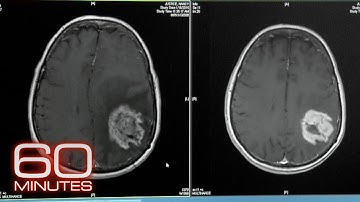

Dr Jaesung Peter Choi and Dr Xiangjian Zheng speak about how Ponatinib successfully targets CCM